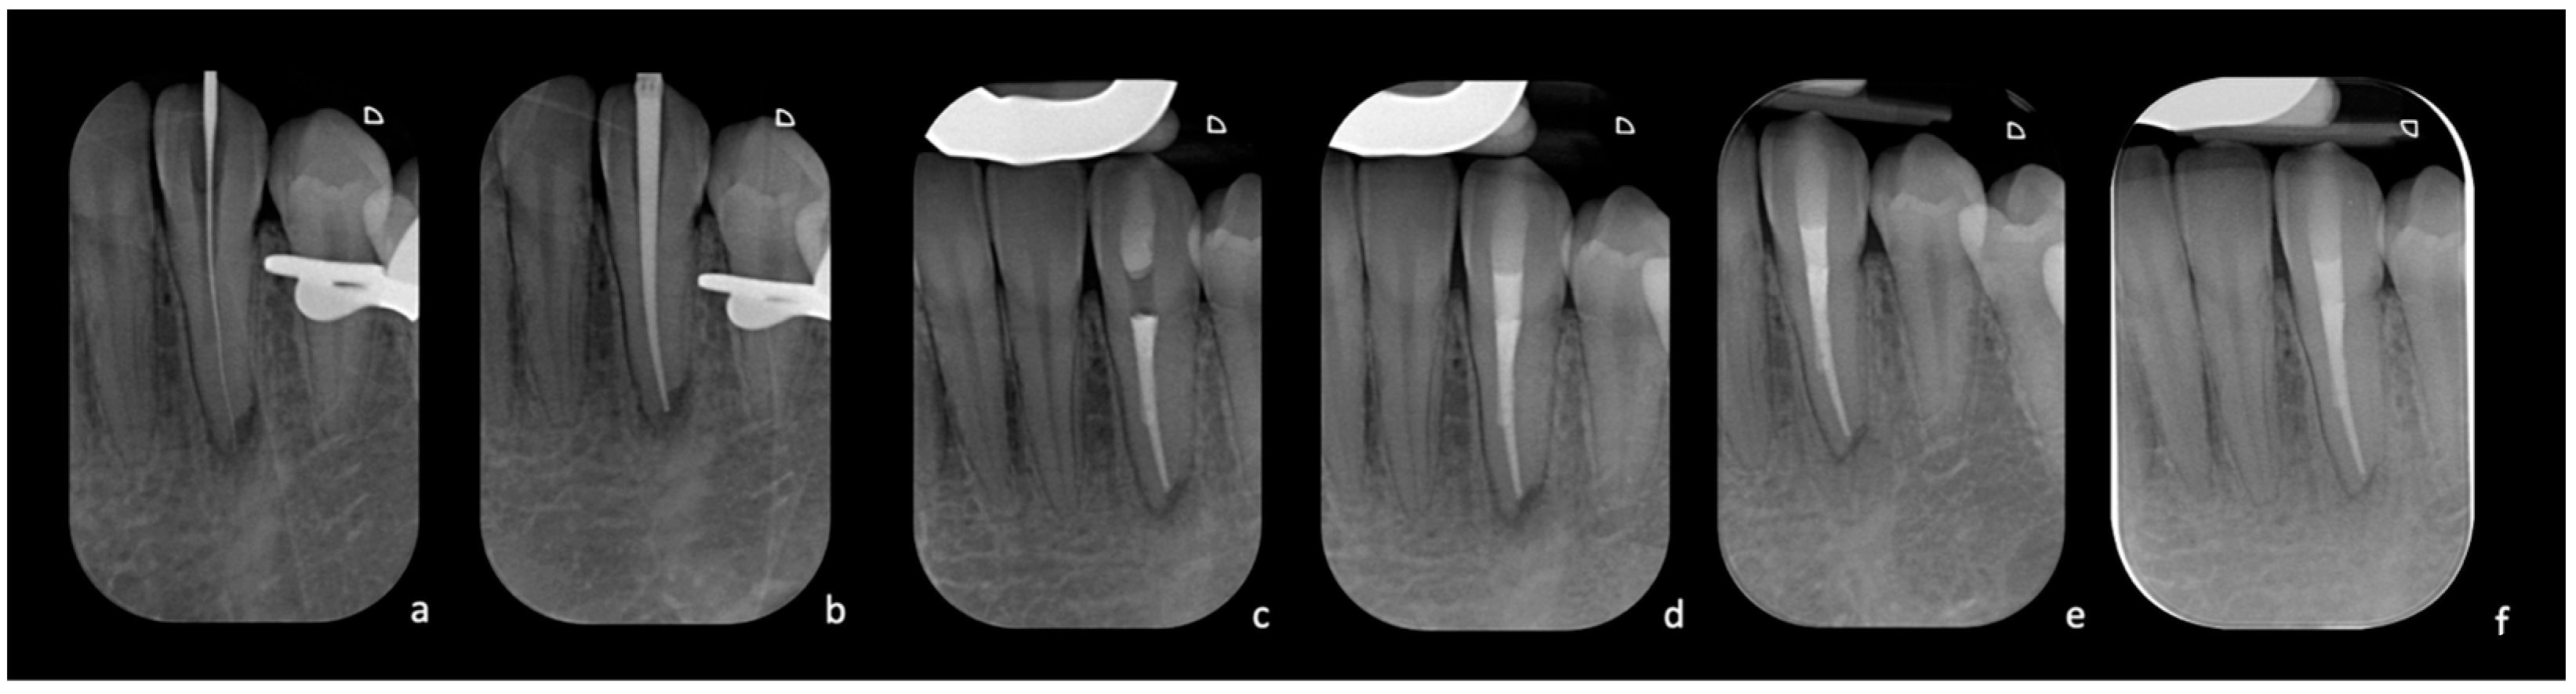

An initial periapical X-ray using the long-cone parallel technique revealed a clearly identifiable root canal space and periapical radiolucency of PAI 3 (changes in bone structure with light mineral loss) (Figure 1a). Tooth 3.3 was diagnosed as necrotic pulp with symptomatic apical periodontitis and was planned for nonsurgical root canal therapy. Considering the pre-operative, X-ray which notably showcased the root canal, a pre-operative CBCT was deemed unnecessary, and it was decided to proceed with the traditional treatment consisting of the freehand ultrasonic technique and a dental operating microscope.

After local anesthesia (Articaine Septanest with adrenaline 1:200,000; Septodont, Saint-Maur-des-Fosses, France), and rubber dam isolation, the access cavity was prepared under a dental operating microscope (Leica M500, Leica Microsystems, Wetzlar, Germany) with a diamond access bur (Dentsply Sirona 851012 FG safe end bur, Dentsply Sirona, Charlotte, NC, USA). Afterwards, an ultrasonic handpiece (Satelec, Acteon, Merignac, France) with an Endodontic Treatment Exploration Ball Diamond Tip ultrasonic tip (Satelec P5® Piezo, Acteon, Merignac, France) was used in endo mode. However, this initial attempt to negotiate the canal led to a small deviation that hindered further progress. Indeed, an intra-operative X-ray with a gutta-percha cone was performed, which showcased a small deviation that was hindering further progress (Figure 1b). Given the expressed desire of the patient to preserve the natural element, a different treatment strategy was proposed.

Figure 1. (a) Pre-operative X-ray; small periapical radiolucent area. (b) Intra-operative X-ray with a gutta-percha cone to evaluate the trajectory of the initial preparation carried out with ultrasonic inserts. It is impossible to reach the canal despite using the operating microscope, and the cone shows that one is proceeding in the wrong direction.

Figure 4. (a) Intra-operative X-ray of the K-file inserted at WL after locating the canal. (b) Intra-operative X-ray with the gutta-percha cone test. (c) Post-operative X-ray with completed root canal filling. (d) Radiograph taken after completing the coronal seal. (e) Radiographic control at three months with signs of improvement of the apical radiolucency. (f) Radiographic follow-up at two years with complete healing.